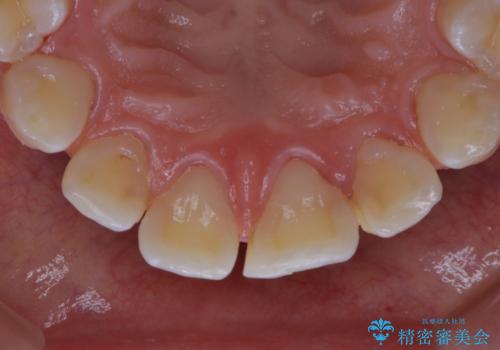

プラーク(細菌の塊)や歯石がたまると歯の表面はザラつきいてきます。そのザラつきは歯周病や虫歯菌の棲家となります。そのまま放置すると、歯肉が腫れてきたり、歯肉から出血したり、口臭が強くでたりします。とくに歯肉の境目は、歯磨きで汚れを除去することが難しく、プラーク(細菌の塊)や歯石が溜まりやすい場所です。

歯並が、がたついている場合はなおさら汚れが溜まりやすいです。矯正治療前や矯正中、定期的にPMTCをすることで、矯正治療中の歯肉トラブルを防ぐことにつながります。